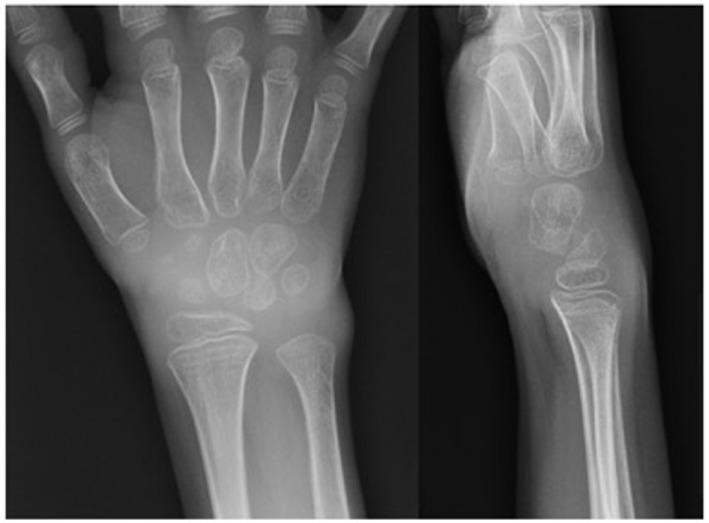

Autoimmune polyendocrinopathy with candidiasis and ectodermal dystrophy (APECED) is a rare disorder of immune dysregulation caused by mutations in the autoimmune regulator () gene. Individuals affected with APECED develop a clinical syndrome characterized by ectodermal abnormalities, autoantibody production, and organ-specific autoimmune manifestations. Inflammatory arthritis is usually not described as a part of the syndrome, and only sporadic cases are reported. We describe the case of a preschool-age girl who presented with hypoparathyroidism, hepatitis, interstitial pneumonitis, and chronic polyarthritis at 4 years of age and was found to have two compound heterozygous disease-associated mutations in the gene. We also conducted a literature review of the main characteristics of inflammatory arthritis in APECED patients. Our case and review demonstrate that (1) inflammatory arthritis, although rare, can be an early manifestation of APECED; (2) the diagnosis of APECED should be considered if mucocutaneous candidiasis, multiple organ-specific autoimmune manifestations, polyendocrinopathy, especially hypoparathyroidism or adrenal failure, or ectodermal dystrophy accompany joint symptoms; and (3) genotyping interpretation should take into account that mutations are found in the 14 exons of the gene, compound heterozygosity is common, and in some cases, only one or no mutated alleles are found.

自身免疫性多内分泌腺病合并念珠菌病和外胚层营养不良(APECED)是一种由自身免疫调节因子(AIRE)基因突变引起的罕见免疫调节紊乱疾病。患有APECED的个体出现一种临床综合征,其特征为外胚层异常、自身抗体产生以及器官特异性自身免疫表现。炎性关节炎通常未被描述为该综合征的一部分,仅报道过散发病例。我们描述了一名学龄前女童的病例,该女童在4岁时出现甲状旁腺功能减退、肝炎、间质性肺炎和慢性多关节炎,并且在AIRE基因中发现了两个复合杂合性疾病相关突变。我们还对APECED患者炎性关节炎的主要特征进行了文献综述。我们的病例及综述表明:(1)炎性关节炎虽然罕见,但可能是APECED的早期表现;(2)如果黏膜皮肤念珠菌病、多种器官特异性自身免疫表现、多内分泌腺病,尤其是甲状旁腺功能减退或肾上腺功能衰竭,或外胚层营养不良伴有关节症状,则应考虑APECED的诊断;(3)基因分型解释应考虑到在该基因的14个外显子中发现突变、复合杂合性很常见,并且在某些情况下,仅发现一个或未发现突变等位基因。